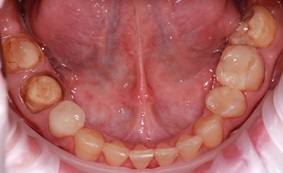

Пациентка С. обратилась с жалобами на щелчки в области наружного слухового прохода слева, дискомфорт при жевании, повышенный тонус жевательной мускулатуры, нарушение эстетического вида фронтальной группы зубов верхней челюсти, сколы композитного материала, желанием индивидуализировать свою улыбку.

Полная эстетическая реабилитация

В процессе диагностического исследования выявлено: наличие несостоятельных композитных реставраций зубов 1.3, 1.2, 1.1, 2.1, 2.2, 2.3, множественные сколы, дебондинг, рецидивирующий кариес. Патологическая генерализованная стираемость легкой степени, некомпенсированная форма, снижение межальвеолярной высоты. Асинхронность движения суставных головок нижней челюсти, сопровождающихся щелчком слева.

Полная эстетическая реабилитация пациента. Оптимальное позиционирование анатомических структур височно-нижнечелюстного сустава. Нормализация функциональной окклюзии, посредством восстановления дефектов зубных рядов

По результату планирования ортопедической реабилитации составлен предварительный план лечения:

1. Выполнения профессиональной гигиены полости рта

2. Изготовление временных эстетических ортопедических конструкций зубов 1.1, .1,2, 1.3, 2.1, 2.2, 2.3

3. Компенсация отсутствующего зуба 4.6 посредством дентальной имплантации.

4. Последовательное восстановление дефекта зубного ряда верхней челюсти безметалловыми конструкциями 1.7, 1.6, 1.5, 1.4, 2.7, 2.6, 2.5, 2.4

5. Восстановление дефектов зубного ряда нижней челюсти безметалловыми конструкциями 3.6 3.7, 4.6, 4.7

6. Изготовление безметалловых конструкций зубов 1.1, 1.2, 1.3 ,2.1 2.2 ,2.3

7. Изготовление оксид-циркониевых виниров зубов 3.3, 3.2, 3.1 4.1 .4.2 ,4.3

8. Изготовление эластичной каппы зубного ряда нижней челюсти, для лучшей адаптации в постреабилитационном периоде.

Использование поляризационного фильтра для оценки монохромности эстетических конструкций в зоне улыбки.